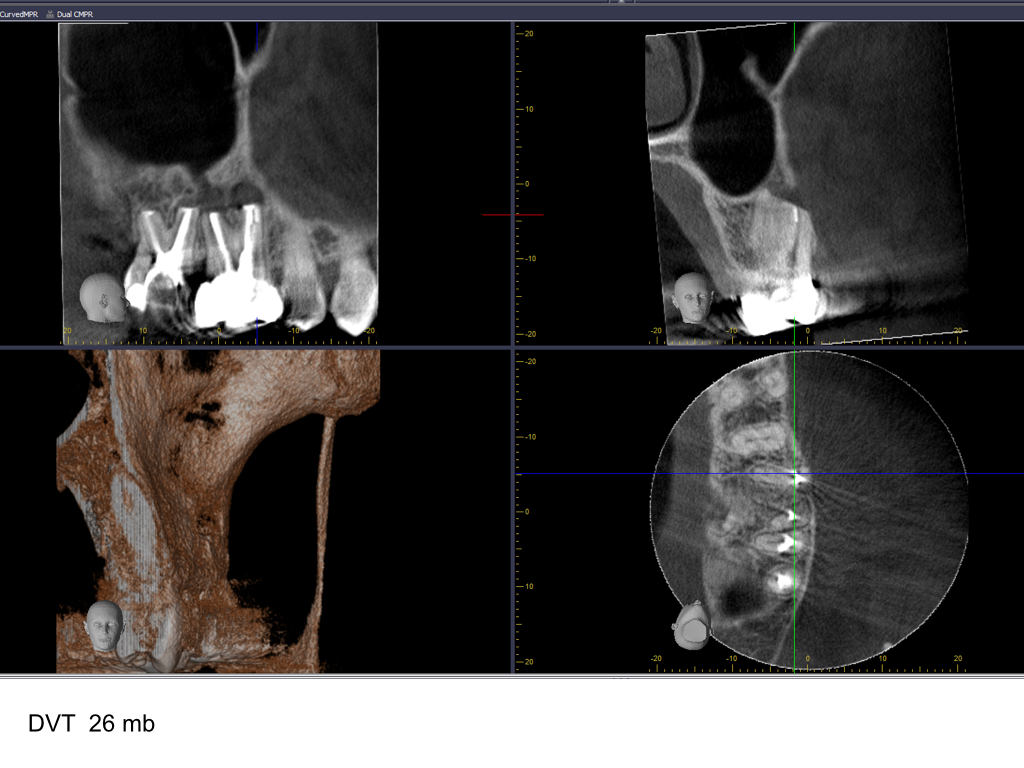

WS15_10.008

1024 × 768

Zustand nach WSR